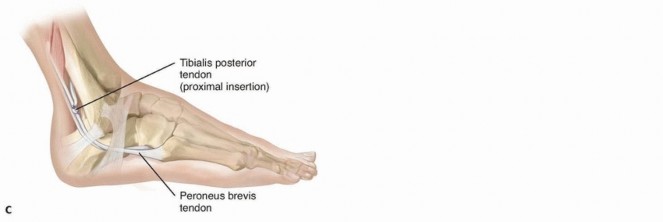

most accurate evaluation, as spasticity is eliminated. Such an examination is always performed at the time of surgery to finalize the treatment plan, as a full passive range of motion is a prerequisite for a tendon transfer.For patients with an equinovarus deformity, the examination focuses on the degree of passive eversion and dorsiflexion. Equinus contracture is often limited to the gastrocnemius muscle but may also involve the soleus muscle.The Silfverskiöld test evaluates the contribution of each component of the gastrocsoleus complex to an equinus contracture, and the amount (in degrees) of passive dorsiflexion is quantified with the knee both flexed and extended. The degree of passive dorsiflexion with the knee extended indicates the absolute magnitude of contracture from the gastrocnemius and soleus. Flexion of the knee relaxes the gastrocnemiusmuscle and allows the contribution of the soleus to be quantified.Selectivity of motor control is commonly impaired in children with cerebral palsy and is tested by asking the patient to contract an isolated muscle group against resistance. This is graded as normal if the patient can isolate the individual muscle and no “overflow” movement is observed in other muscle groups of the same limb. Most commonly, movements of more than one muscle group, or the entire limb, are elicited when testing individual muscle groups. ## IMAGING AND OTHER DIAGNOSTIC STUDIES Although imaging studies are not routinely obtained, plain radiographs of the foot may be helpful in the presence of a fixed deformity.Weight-bearing anteroposterior (AP) and lateral views are reviewed, and a Harris heel view may be considered to evaluate the degree of hindfoot varus in the weight-bearing position.Instrumented motion analysis (gait analysis) is used in many centers to assist with surgical decision making.Slow-motion video is an important component of the assessment and supplements the findings on observational gait analysis.Dynamic electromyelography (EMG) monitors the electrical activity of the tibialis posterior and tibialis anterior throughout the gait cycle, determining whether individual muscles act out of phase or whether they arecontinuously active throughout the gait cycle. 13 Although a surface electrode may be used to assess the tibialis anterior, monitoring of the tibialis posterior requires insertion of a fine needle electrode.One study determined that the deformity was due to the tibialis posterior in 33%, the tibialis anterior in 34%, or both (31%). 9Findings on pedobarography include increased pressure across the lateral midfoot, decreased pressure on the heel at the time of initial contact, and increased pressure on the lateral border of the foot throughout stance phase. ## NONOPERATIVE MANAGEMENT Specific aspects within a comprehensive physical therapy program include stretching exercises to maintain or improve range of motion and strengthening exercises to reduce dynamic muscle imbalance.An ankle-foot orthosis is often required to maintain alignment of the ankle and hindfoot during ambulation.The orthotic facilitates clearance during swing phase by maintaining the foot in a neutral position, prepositions the foot for initial contact with the ground, and promotes stability during stance phase.Night splinting may help to prevent myostatic contracture.Injection of botulinum toxin A (Botox or Dysport) into the tibialis posterior, the gastrocsoleus, or both results in a reversible chemical denervation that decreases spasticity for about 3 to 6 months.In addition to reducing dynamic muscle imbalance, a temporary reduction in spasticity may facilitate stretching exercises, improve bracing tolerance, and delay the need for surgical intervention. ## SURGICAL MANAGEMENT Surgical treatment of the spastic equinovarus foot is offered when the deformity impairs ambulation, interferes with bracing, or both.The goal of tendon transfer is to balance the muscle forces across the hindfoot to maintain a neutral positionduring the swing and stance phases of gait. A split tendon transfer is preferred as transfer of the entire tendon is associated with a significant risk of overcorrection.A normal passive range of motion is a prerequisite. In the presence of fixed soft tissue or bony deformity, concomitant muscle lengthening, with or without osteotomy, may be required to restore motion and alignment.Although an instrumented motion analysis with dynamic EMG will enable the treating surgeon to identify whether the tibialis posterior, the tibialis anterior, or both is/are contributing to the deformity, this technology is not always available. The clinical indications suggested for split tibialis posterior tendon surgery include hindfoot varus during both the stance and swing phases of gait. In contrast, overactivity of the tibialis anterior typically produces varus/supination of the midfoot/forefoot during swing phase.It has been suggested that the procedure be delayed until at least 4 to 6 years of age, and one recent report suggested that consideration should be given to delaying split tendon transfer beyond the age of 8 years ifpossible as there may be a greater risk of recurrence. 2Lengthening of the tibialis posterior muscle may be considered in milder deformities, especially in young patients. Techniques include a distal Z-lengthening or a proximal intramuscular recession. Recognize that it may be very difficult to perform a split tendon transfer if a Z-lengthening has been performed previously.Several techniques have been described for split tibialis posterior transfer.The most common involves transferring the split tendon (posterior to the tibia and fibula) to the peroneus brevis, either at its insertion or just behind the lateral malleolus. This approach focuses on balancing inversion-eversion but does not address dorsiflexion weakness ( FIG 1).An alternate technique, which may be considered when there is inadequate active dorsiflexion, involves anterior transfer of the split tendon through the interosseous membrane to the peroneus brevis ( FIG 2A,B) or the lateral cuneiform (FIG 2C).

### FIG 1 • In the technique described by Kaufer,5 the split tendon is routed behind the tibia and fibula ( A) and inserted into the peroneus brevis tendon ( B). C. Alternatively, the split tendon can be woven into the peroneus brevis just behind the lateral malleolus. This approach is easier and works as well when the tendon is not long enough.

### FIG 2 • In the technique described by Mulier et al,11 the split tendon is passed through the interosseous membrane ( A) and through a subcutaneous tunnel to insert into the peroneus brevis tendon ( B). C. Saji et al 16 transferred the split tendon through the interosseous membrane into the lateral cuneiform.